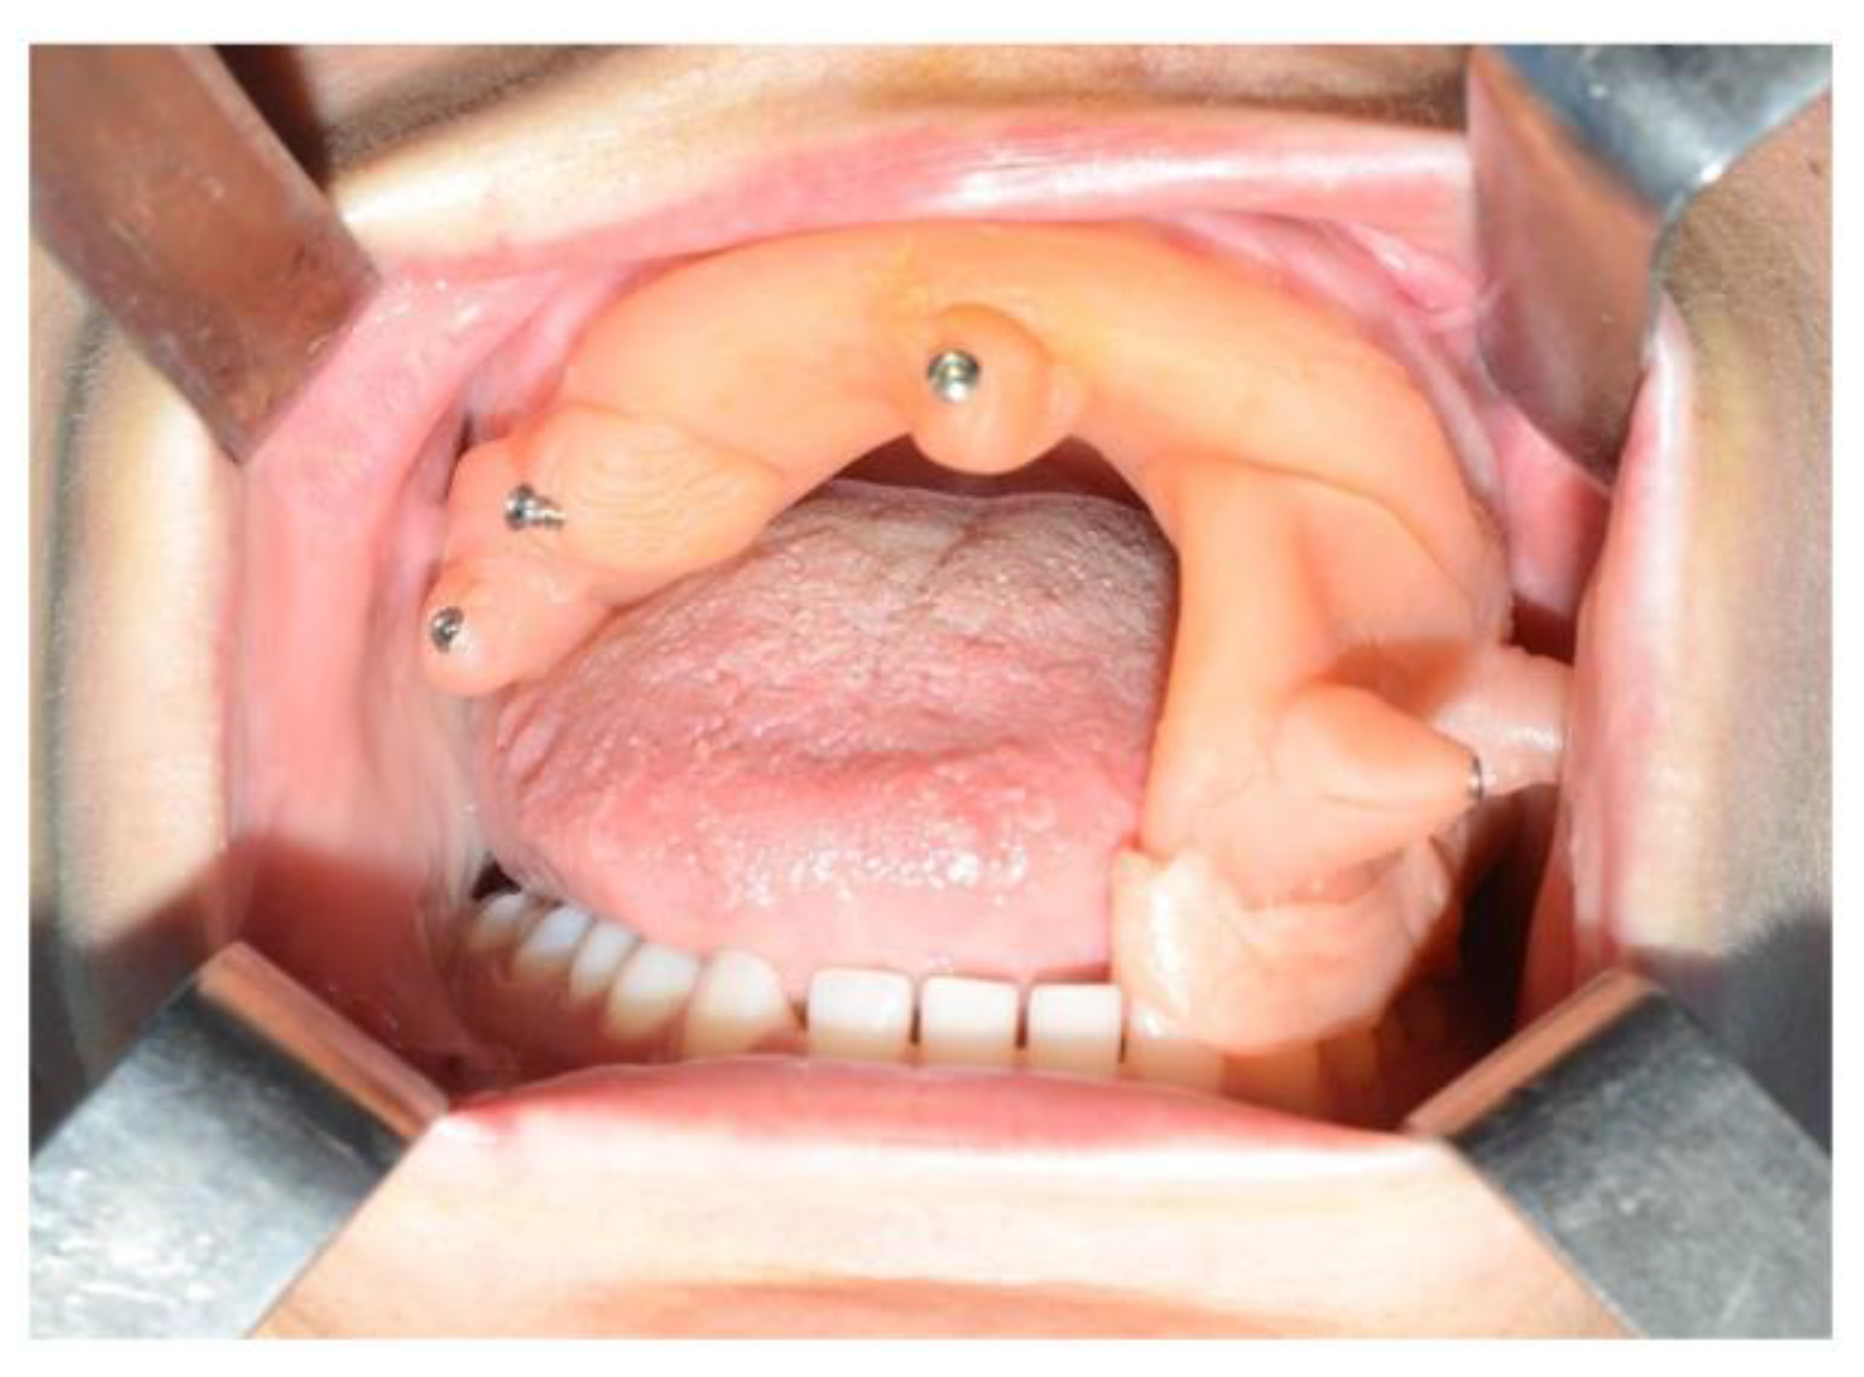

In light of the suspicion of an ameloblastoma recurrence, surgical removal was recommended, opting for the use of tracked instruments with surgical navigation. A maxillary bite was created, followed by the attachment of 5 screws with varying spatial orientations that would function as fiducial markers. This bite was employed to maintain the mandible in a consistent position both during the preoperative CT scan acquisition and throughout the entire surgical procedure (Figure 13).

Figure 13.

Intraoperative placement of the same bite used for acquiring mandibular CT scan images. The bite ensures the mandible remains in the same position as during the virtual surgical planning.

During the surgical procedure, the Dynamic Reference Frame (DRF) was positioned in the right parietal bone, and the positions of the screws on the bite were recorded as fiducial markers. The same bite used during the CT image acquisition was utilised for this purpose. The navigation accuracy was less than 0.5 mm. The piezoelectric was registered by attaching a tracking tool with three reflective spheres to the handpiece, and the tip of the piezoelectric was marked and utilised as a reference point for navigation. The navigation accuracy was found to be less than 1 mm.